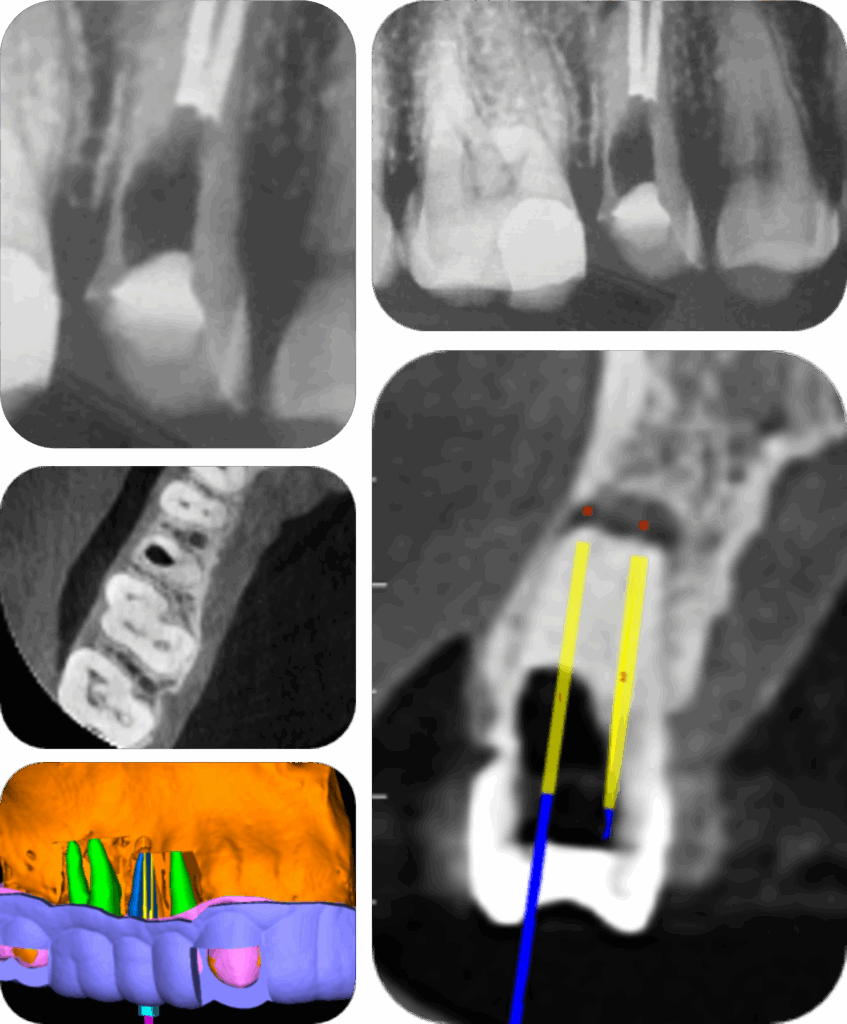

ENDODONTIA GUIADA DE PRECISÃO

ENDODONTIA GUIADA DE PRECISÃO é a técnica que através do planejamento 3D possibilita o desenho e impressão em resina de um guia que será posicionado/assentado sobre a arcada dentária com acesso ao conduto por onde adentra uma broca especial para ultrapassar obstruções (como calcificações), que outros métodos tradicionais da Endodontia (como instrumentação, ultrassom) não conseguem remover.

No início de 2018 percebemos a necessidade de desenvolver instrumental especifico para essa técnica endodôntica, quando tivemos solicitação de Endoguide para acesso de um incisivo lateral inferior calcificado. A broca que se utilizava era de implantodontia, com dimensões de 20 mm x 1,3 mm. Esta broca, além de diâmetro acentuado para raízes com volume reduzido (como incisivos laterais e quartos canais); também apresentava e apresenta limitação no comprimento de trabalho, por ser muito curta.